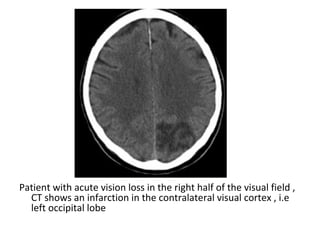

Patient with acute vision loss in the right half of the visual field ,

CT shows an infarction in the contralateral visual cortex , i.e

left occipital lobe

PCA infarction , notice the loss of gray / white matter differentiation in

the region of the left occipital lobe